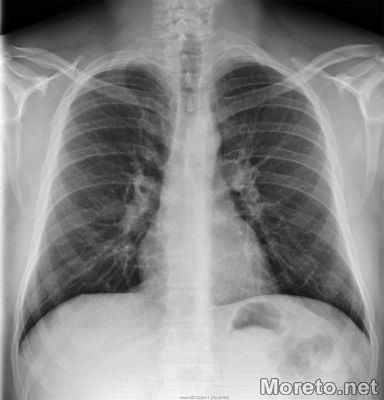

Муковисцидозата е най-разпространеното рядко генетично заболяване в света, от което в България страдат около 200 души, предимно деца и младежи. Засяга главно белите дробове и храносмилателната система. Секретите в дробовете и панкреаса са необичайно гъсти и причиняват затруднено дишане, кашлица и влошено храносмилане. Пневмониите и престоите в болница са чести. Родителите са здрави, затова често диагнозата се поставя по-късно и лечението започва, когато заболяването е напреднало. С времето се увреждат и другите системи на организма.